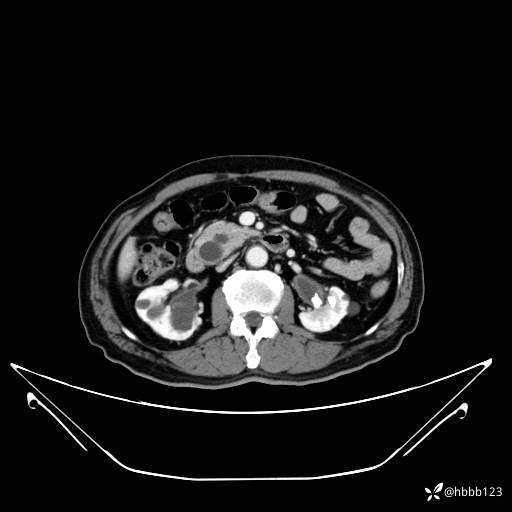

门脉期: